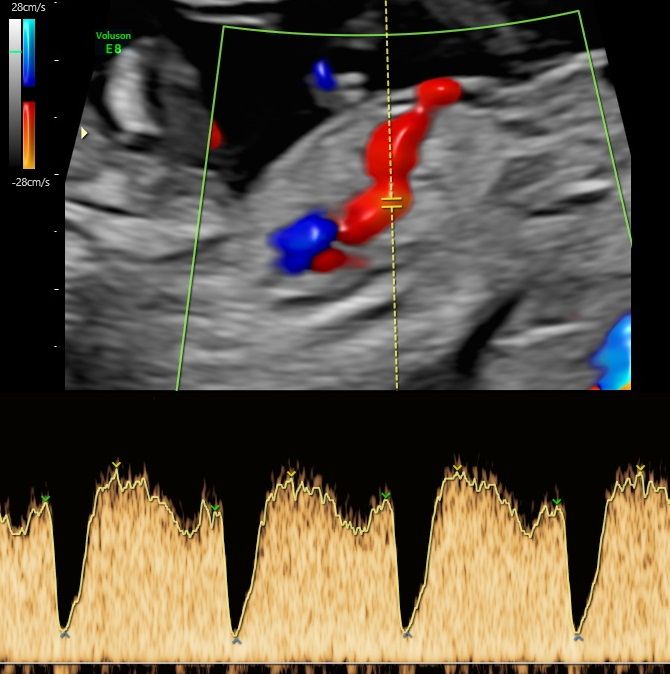

-certyfikat The Fetal Medicine Foundation (FMF) w zakresie badań prenatalnych w 11–13+6 tygodniu ciąży – przezierność karku u płodu (NT); kość nosowa u płodu (NB); przepływ w przewodzie żylnym u płodu (DV); przepływ na zastawce trójdzielnej (TR) oraz oceny ryzyka wystąpienia preeklampsji (stanu przedrzucawkowego) w ciąży.

Od 2022 współpracuje z Zakładem Kardiologii Prenatalnej ICZMP w Łodzi (pod kierownictwem prof Marii Respondek-Liberskiej) w zakresie diagnostyki i dalszej opieki specjalistycznej nad płodami z wrodzonymi wadami serca.

Zdjęcia i filmy